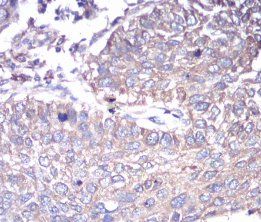

GNAS Mouse Monoclonal antibody[2A2B7]

Immunogen :   Purified recombinant fragment of human GNAS (AA: 42-188) expressed in E. Coli.

IHC    1/200 - 1/1000